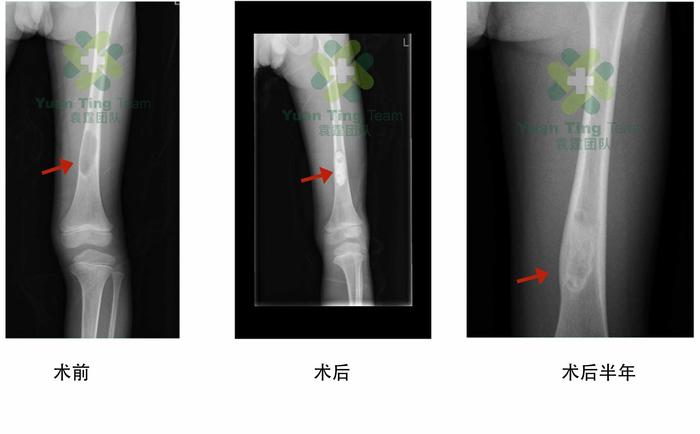

这是一例我们医疗小组的骨囊肿微创手术病例。

从以上图片不难看出,术后半年原囊肿处的骨密度与正常骨几乎无差别。患儿活动感觉皆与正常小朋友无异。不过需要注意的事,并不是所有的骨囊肿都可以微创手术,具体的病情,还是要携带相关影像学资料,到骨肿瘤科就诊。